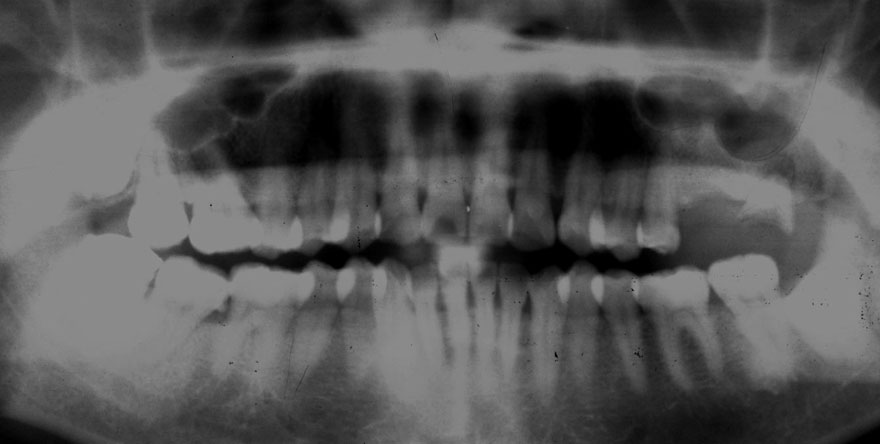

初診時 45歳 女性 平均歯槽骨喪失量:1.94mm

26年後 71歳

平均歯槽骨喪失量:2.16mm

26年間喪失量:-0.22mm

年間喪失速度:-0.008mm

(ケア頻度:1.56ヵ月ごと)